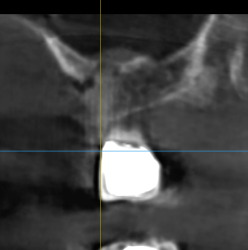

How do you ensure your graft gets to the apex? I completed site preservation today and it is the first time I have done it since residency (2021). The graft in some areas that you see in the CBCT the graft didnt get to the apex? How will this effect implant placement later on? Do you place a little graft at a time, use perio probe then add…